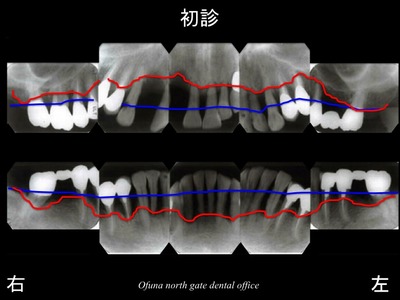

以下のレントゲン写真は、重度歯周病で骨吸収が起こっている方です。

骨吸収が分かりやすいように 骨吸収の状態を線で書いてみましょう!

以下の赤線は、骨吸収が起こった現在の状態です。

それでは、もともと骨吸収が起こる前はどの程度骨があったのでしょうか?

以下の青線は、骨吸収を起こす前の状態です。

これらの線を重ね合わせてみましょう。

さらに骨吸収前(健康な状態)と骨吸収が起こった後が比較しやすいと思います。

つまり、先ほどのレントゲンの赤線が青線に戻ることはないのです。